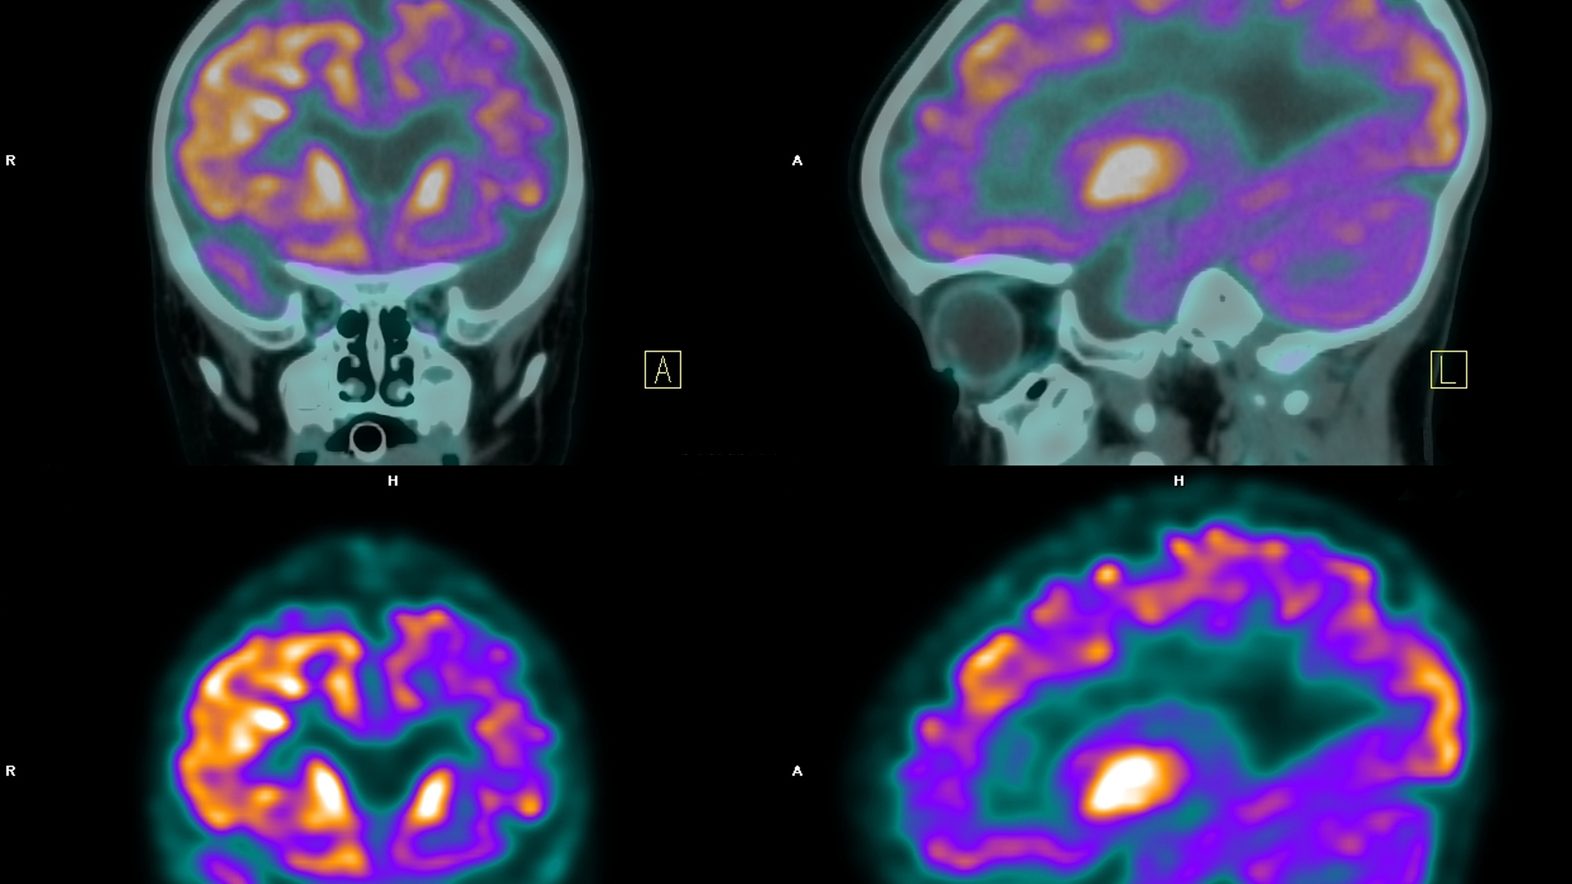

L’idée des scientifiques consiste à étudier les sillons corticaux, des circonvolutions du cerveau qui en vieillissant ont tendance à s’élargir et du même coup, diminuent l’épaisseur du cortex. D’après de précédentes recherches dirigées par Maxime Bertoux, chercheur à l’Inserm et auteur principal de cette nouvelle étude, l’élargissement des sillons corticaux est plus rapide chez les malades de l’Alzheimer. L’étape suivante était donc de déterminer si ce phénomène pouvait constituer un élément pour identifier la maladie.

Cette technique a permis d’explorer 18 régions de chaque hémisphère cérébral et d’évaluer la largeur et l’épaisseur de leurs sillons. Les scientifiques ont également effectué les mesures usuelles du volume de plusieurs régions cérébrales et de l’épaisseur du cortex, afin de comparer les méthodes. Enfin, ils ont utilisé un algorithme afin de comparer et d’évaluer l’état de santé de chaque participant (y compris les personnes non malades).